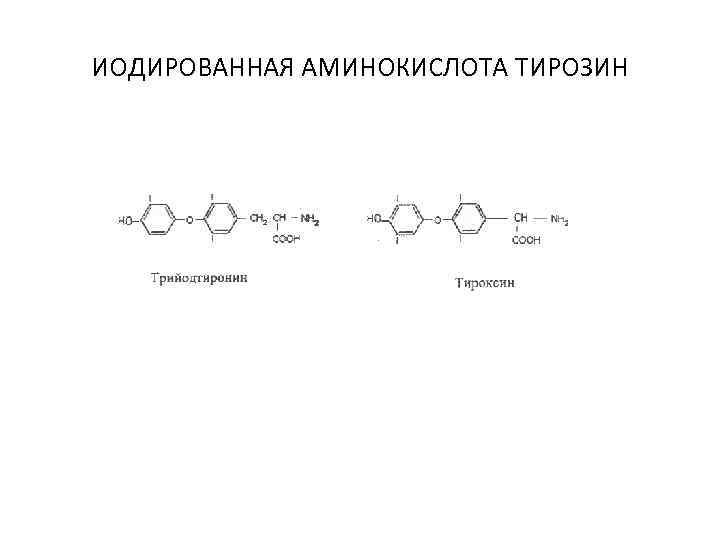

ИОДИРОВАННАЯ АМИНОКИСЛОТА ТИРОЗИН

ИОДИРОВАННАЯ АМИНОКИСЛОТА ТИРОЗИН

Гормоны щитовидной железы 1. Иодсодержащие гормоны (тироксин, трийодтиронин) • Энергетический обмен (ускоряют окислительные процессы) • Стимуляция роста тела и развития центральной нервной системы

Гормоны щитовидной железы 1. Иодсодержащие гормоны (тироксин, трийодтиронин) • Энергетический обмен (ускоряют окислительные процессы) • Стимуляция роста тела и развития центральной нервной системы